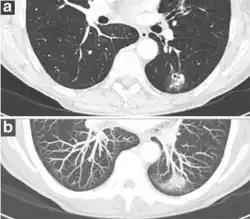

- Margin morphology: a spiculated margin is a risk factor for cancer.[8] Benign causes tend to have a well defined border, whereas lobulated lesions or those with an irregular margin extending into the neighbouring tissue tend to be malignant.[10] In particular, spiculations are highly predictive of malignancy with a positive predictive value up to 90%.[9] Also, a "notch sign", which is an abrupt indentation of the nodule, increases the risk of cancer, but may also be found in granulomatous diseases.[9]

-

subpleural nodule.[9] -

Round well-delineated solid lung nodule with smooth border.[9] -

Lobulated nodule.[9] -

Spiculated lung nodule.[9] -

A "notch sign".[9] -

A triangular perifissural node can be diagnosed as a benign lymph node.[9]